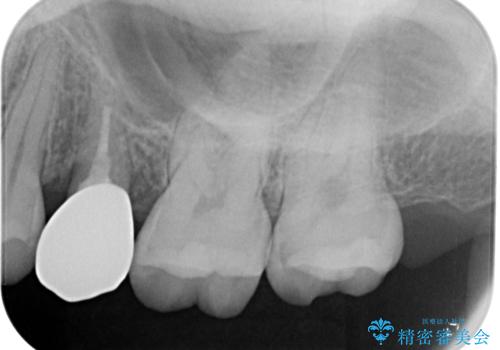

左上の七番目と六番目の歯と歯が接するところに虫歯をレントゲン上で確認できました。

噛み合わせが強く、以前にも当院で右上でゴールドインレーにより治療をされていたのでゴールドインレーにて治療しました。